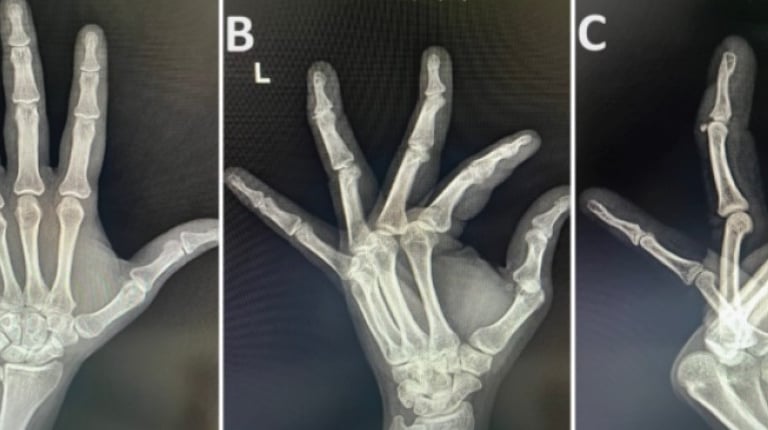

Primary Aneurysmal Bone Cyst of the Phalanx

An aneurysmal bone cyst (ABC) is a benign tumor of bone that constitutes less than 2% of all bone tumors. Among these, less than 5% of ABCs occur in hand. ABC occurs in the first two decades of life, the second decade being the most common. An ABC occurring in the bones of the hand is a rare entity and involves the metacarpals or proximal phalanges. We found curettage and Kirschner wires stabilization without additional bone grafting to be a viable option in treating ABC of the phalanx in a child.